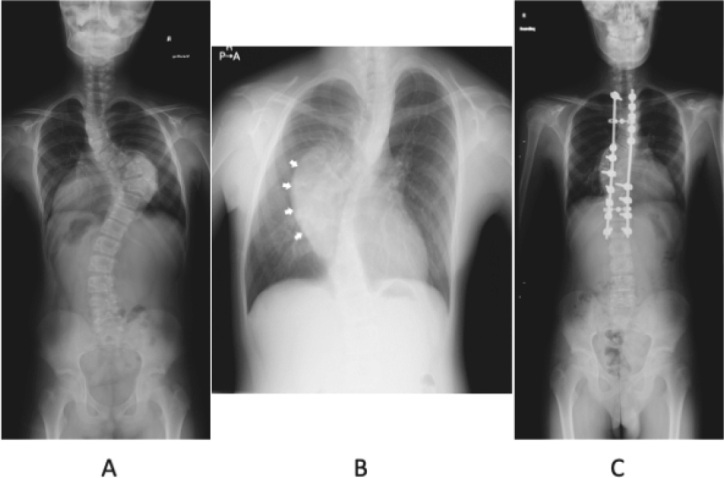

神经节神经瘤是一种罕见的良性肿瘤,起源于交感神经系统。肿瘤的表现是可变的,与青少年胸侧凸有关。在此,我们提出两个病例报告和文献综述。这两例患者分别为10岁和13岁,无肌肉疼痛或无力症状,通过影像学筛查偶然发现神经节神经瘤。两名患者都接受了两阶段的手术。第一阶段涉及肿瘤脱离脊髓,同时从后侧进行畸形矫正手术。第二阶段是通过前路切除神经节神经瘤,没有神经系统问题。两个阶段的手术是必要的切除肿瘤和纠正畸形,从而避免神经问题,同时建立病理诊断。从后路开始被证明是安全且更有效的。

Ganglioneuromas are rare benign tumors that arise from the sympathetic nervous system. The presentation of tumors is variable and associated with adolescent thoracic scoliosis. Herein, we present two case reports and a review of literature. The two cases involved 10 and 13-year-old patients who were asymptomatic for muscle pain or weakness, and ganglioneuromas were incidentally detected through imaging screening. Both patients underwent a two-stage surgery. The first stage involved detachment of the tumor from the spinal cord and simultaneously performing deformity correction surgery from the posterior aspect. The second stage was resection of the ganglioneuroma through the anterior approach without neurological problems. A two-stage surgery was necessary to excise the tumor and correct the deformity, thereby avoiding neurological problems and concurrently establish a pathological diagnosis. Commencing with the posterior approach proved to be safe and was more effective.